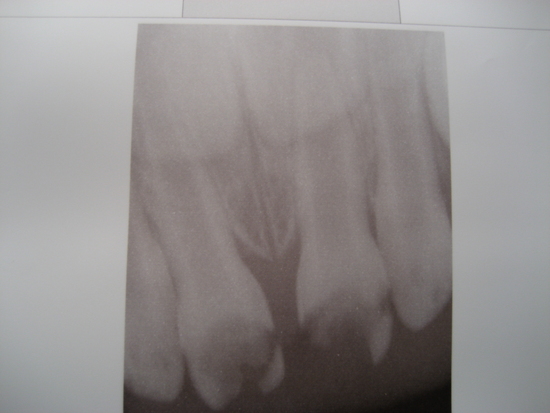

Алина,задравствуйте еще раз! Во-первых,спасибо Вам за предыдущий ответ http://www.babyblog.ru/community/post/stomatolog_consult/1690783, а во-вторых сразу же еще один вопрос. 29.09.2011 мы ходили в очередную стоматологию(надо сказать,самую дорогую и элитную в нашем городе,ходили,потому что там есть возможность вылечить зубы под общим наркозо). Диагноз неутешителен,6 зубов с кариесом на лечение, 2 передних резца с пульптом на удаление...Врач сказала,что началось воспаление в корне зуба, а это может значительно повлиять на рост и качество постоянных зубов. На все мои уговоры о попытках пролечить данные зубы, был получен ответ,что иного выхода,как удаление нет..((( Честно говоря, я в сомнениях.. Прошу Вашего независимого мнения по этому поводу. Выкладываю снимок наших передних зубиков. И еще,это очень срочно,так как уже в понедельник начинаем сдавать все анализы на подготовку. Спасибо Вам большое заранее

Я бы лечила. Удалить нервы и заложить лечебную пасту. Пусть и на несколько месяцев. Уже тогда воспалительный процесс остановится. После сделать контрольный снимок и решить, но больше, чем увера, что результат Вас обрадует.

А потом временную пасту в каналах заменить на постоянную.